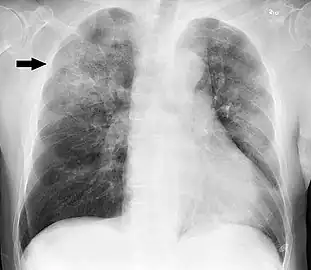

Chest X-ray of a pneumonia caused by influenza and Haemophilus influenzae, with patchy consolidations, mainly in the right upper lobe (arrow)

X-ray presentations of pneumonia may be classified as lobar pneumonia, bronchopneumonia, lobular pneumonia, and interstitial pneumonia.[66] Bacterial, community-acquired pneumonia classically show lung consolidation of one lung segmental lobe, which is known as lobar pneumonia.[34] However, findings may vary, and other patterns are common in other types of pneumonia.[34] Aspiration pneumonia may present with bilateral opacities primarily in the bases of the lungs and on the right side.[34] Radiographs of viral pneumonia may appear normal, appear hyper-inflated, have bilateral patchy areas, or present similar to bacterial pneumonia with lobar consolidation.[34] Radiologic findings may not be present in the early stages of the disease, especially in the presence of dehydration, or may be difficult to interpret in the obese or those with a history of lung disease.[21] Complications such as pleural effusion may also be found on chest radiographs. Laterolateral chest radiograph can increase the diagnostic accuracy of lung consolidation and pleural effusion.[33]